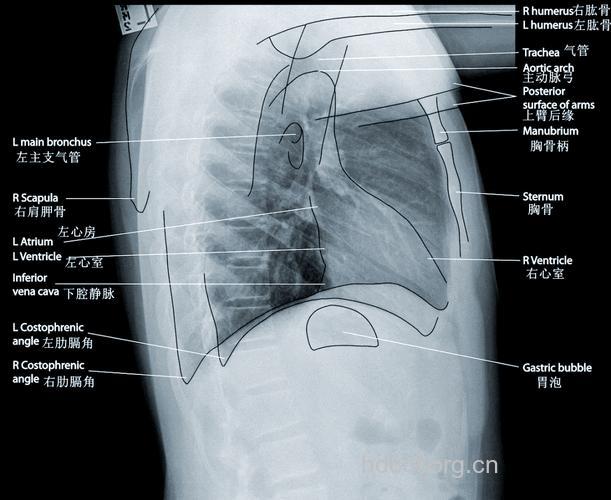

心脏后对五到八胸椎,前对二到六肋骨。(补心胸比。)我们在读片的时候经常听到有一个概念叫“主动脉结”,它是什么意思呢?在哪里呢?主动脉结就是主动脉弓由右转向左出突出于胸骨左缘的地方,它平对左胸第二肋软骨。这里我还想说一点,那就是肺动脉段的位置,肺动脉段位于主动脉结下方,对判断肺动脉高压很有意义。

一般右肋膈顶在第五肋前端至第六肋前间水平,由于右侧有肝脏的存在,右膈顶通常要比左侧高一到两厘米。意义:胸腔或腹腔压力的改变可以改变膈肌的位置如气胸时膈位置可以压低;膈神经麻痹出现矛盾呼吸。正常的肋膈角是锐利的,如果肋膈角变钝则有胸腔有积液或积血存在,那我们如何来大体判断积液的量呢?一般说肋膈角变钝:积液300ml;肋膈角闭锁:500ml。

什么叫心尖下移?有什么意义?心影的最外缘在膈平面以上称心尖上翘,代表右心室肥厚;反之心影的最外缘在膈平面以下称心尖下移,代表左心室肥厚。

一点窍门教给大家:心前三角变小则右心室大;心后三角大则左心室大。